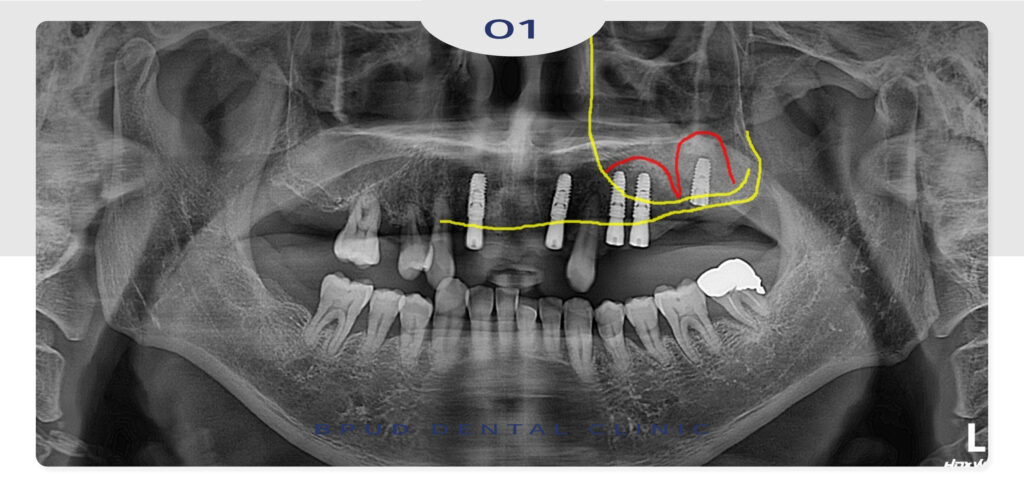

왼쪽 위 어금니 부위는 골소실이 많이

진행되어 상악동 거상술을 통해

많은 양의 뼈를 이식하여 임플란트를

진행하시기로 하였는데요.

상악동 거상술은 상악동이라는 공기 주머니가

임플란트 식립을 방해하는 경우 뼈를 증대시키는

수술적 방법으로 방법은 두가지로 나누어 집니다.

필요한 골 높이가 비교적 많을 경우에는 측방 접근법,

소량인 경우에는 치조정 접근법이 사용되는데요.

측방 접근법은 치아가 없는 부위의 측면에

작은 창을 내고 상악동 점막을 들어올린 후

뼈를 이식하는 방법이며 비교적 많은 양의

골이 필요한 경우 주로 시행 됩니다.

반면, 치조정 접근법은 비교적 침습이 적고

회복이 빠르지만 적용할 수 있는 케이스가 제한적인데요.

환자분께는 측방 접근법을 사용하였습니다.